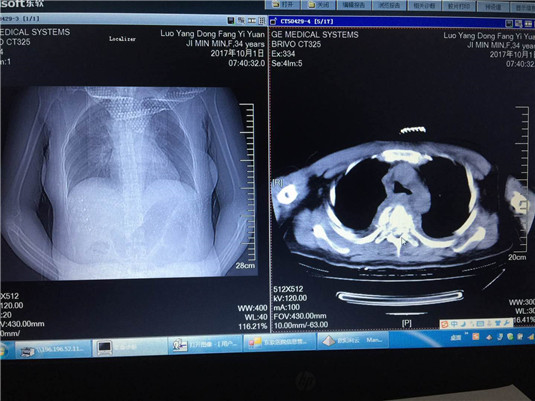

10月1日上午9:00,一位34岁女性患者,因汽车追尾导致重伤急诊入院,患者自胸部以下感觉已丧失,双下肢不能活动。急诊行胸椎MRI、CT检查示:胸5椎体爆裂性骨折,胸4椎体骨挫伤;多发性肋骨骨折,创伤性胸腔积液,立即转入骨科二病区住院治疗。

当机立断,骨科二病区主任陈月明立即成立急诊手术小组,副主任医师欧阳利云与家属沟通后,立即进行手术计划拟定。患者血压94/66,多发性肋骨骨折,创伤性胸腔积液,前纵隔血肿形成。考虑到患者目前实际情况,为防止患者创伤性休克。 通过病情一一研讨,决定给予患者抗休克补液支持治疗,先稳定生命体征再给予手术治疗。